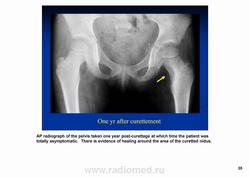

Остеоидная остема.

Диагностика и дифференциальная диагностика.